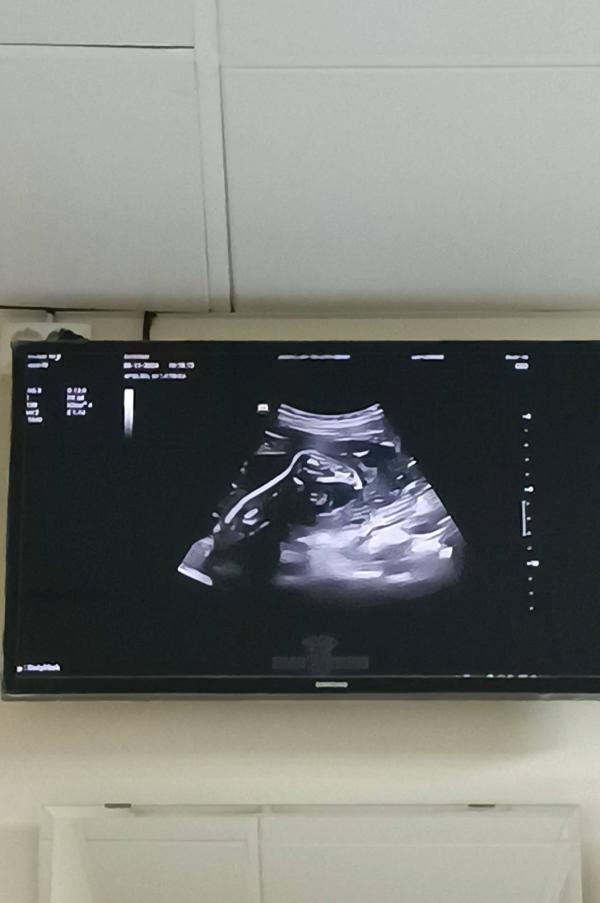

Сводила своё пузо на УЗИ 😅 плацента с краевого предлежания переползла на 2.1 мм выше зева. Кардинально ничего не изменилось, всё так же маячит на горизонте КС, но эта гора хотя бы сдвинулась с места. Всё таки надежда умирает последней и возможно чудесным образом она еще поднимется. Я такое читала, что буквально за несколько недель до родов всё поднималось и разрешали ЕР. Ну по крайней мере надеюсь госпитализацию назначат хотя бы не в 30 недель, а позднее 🙏